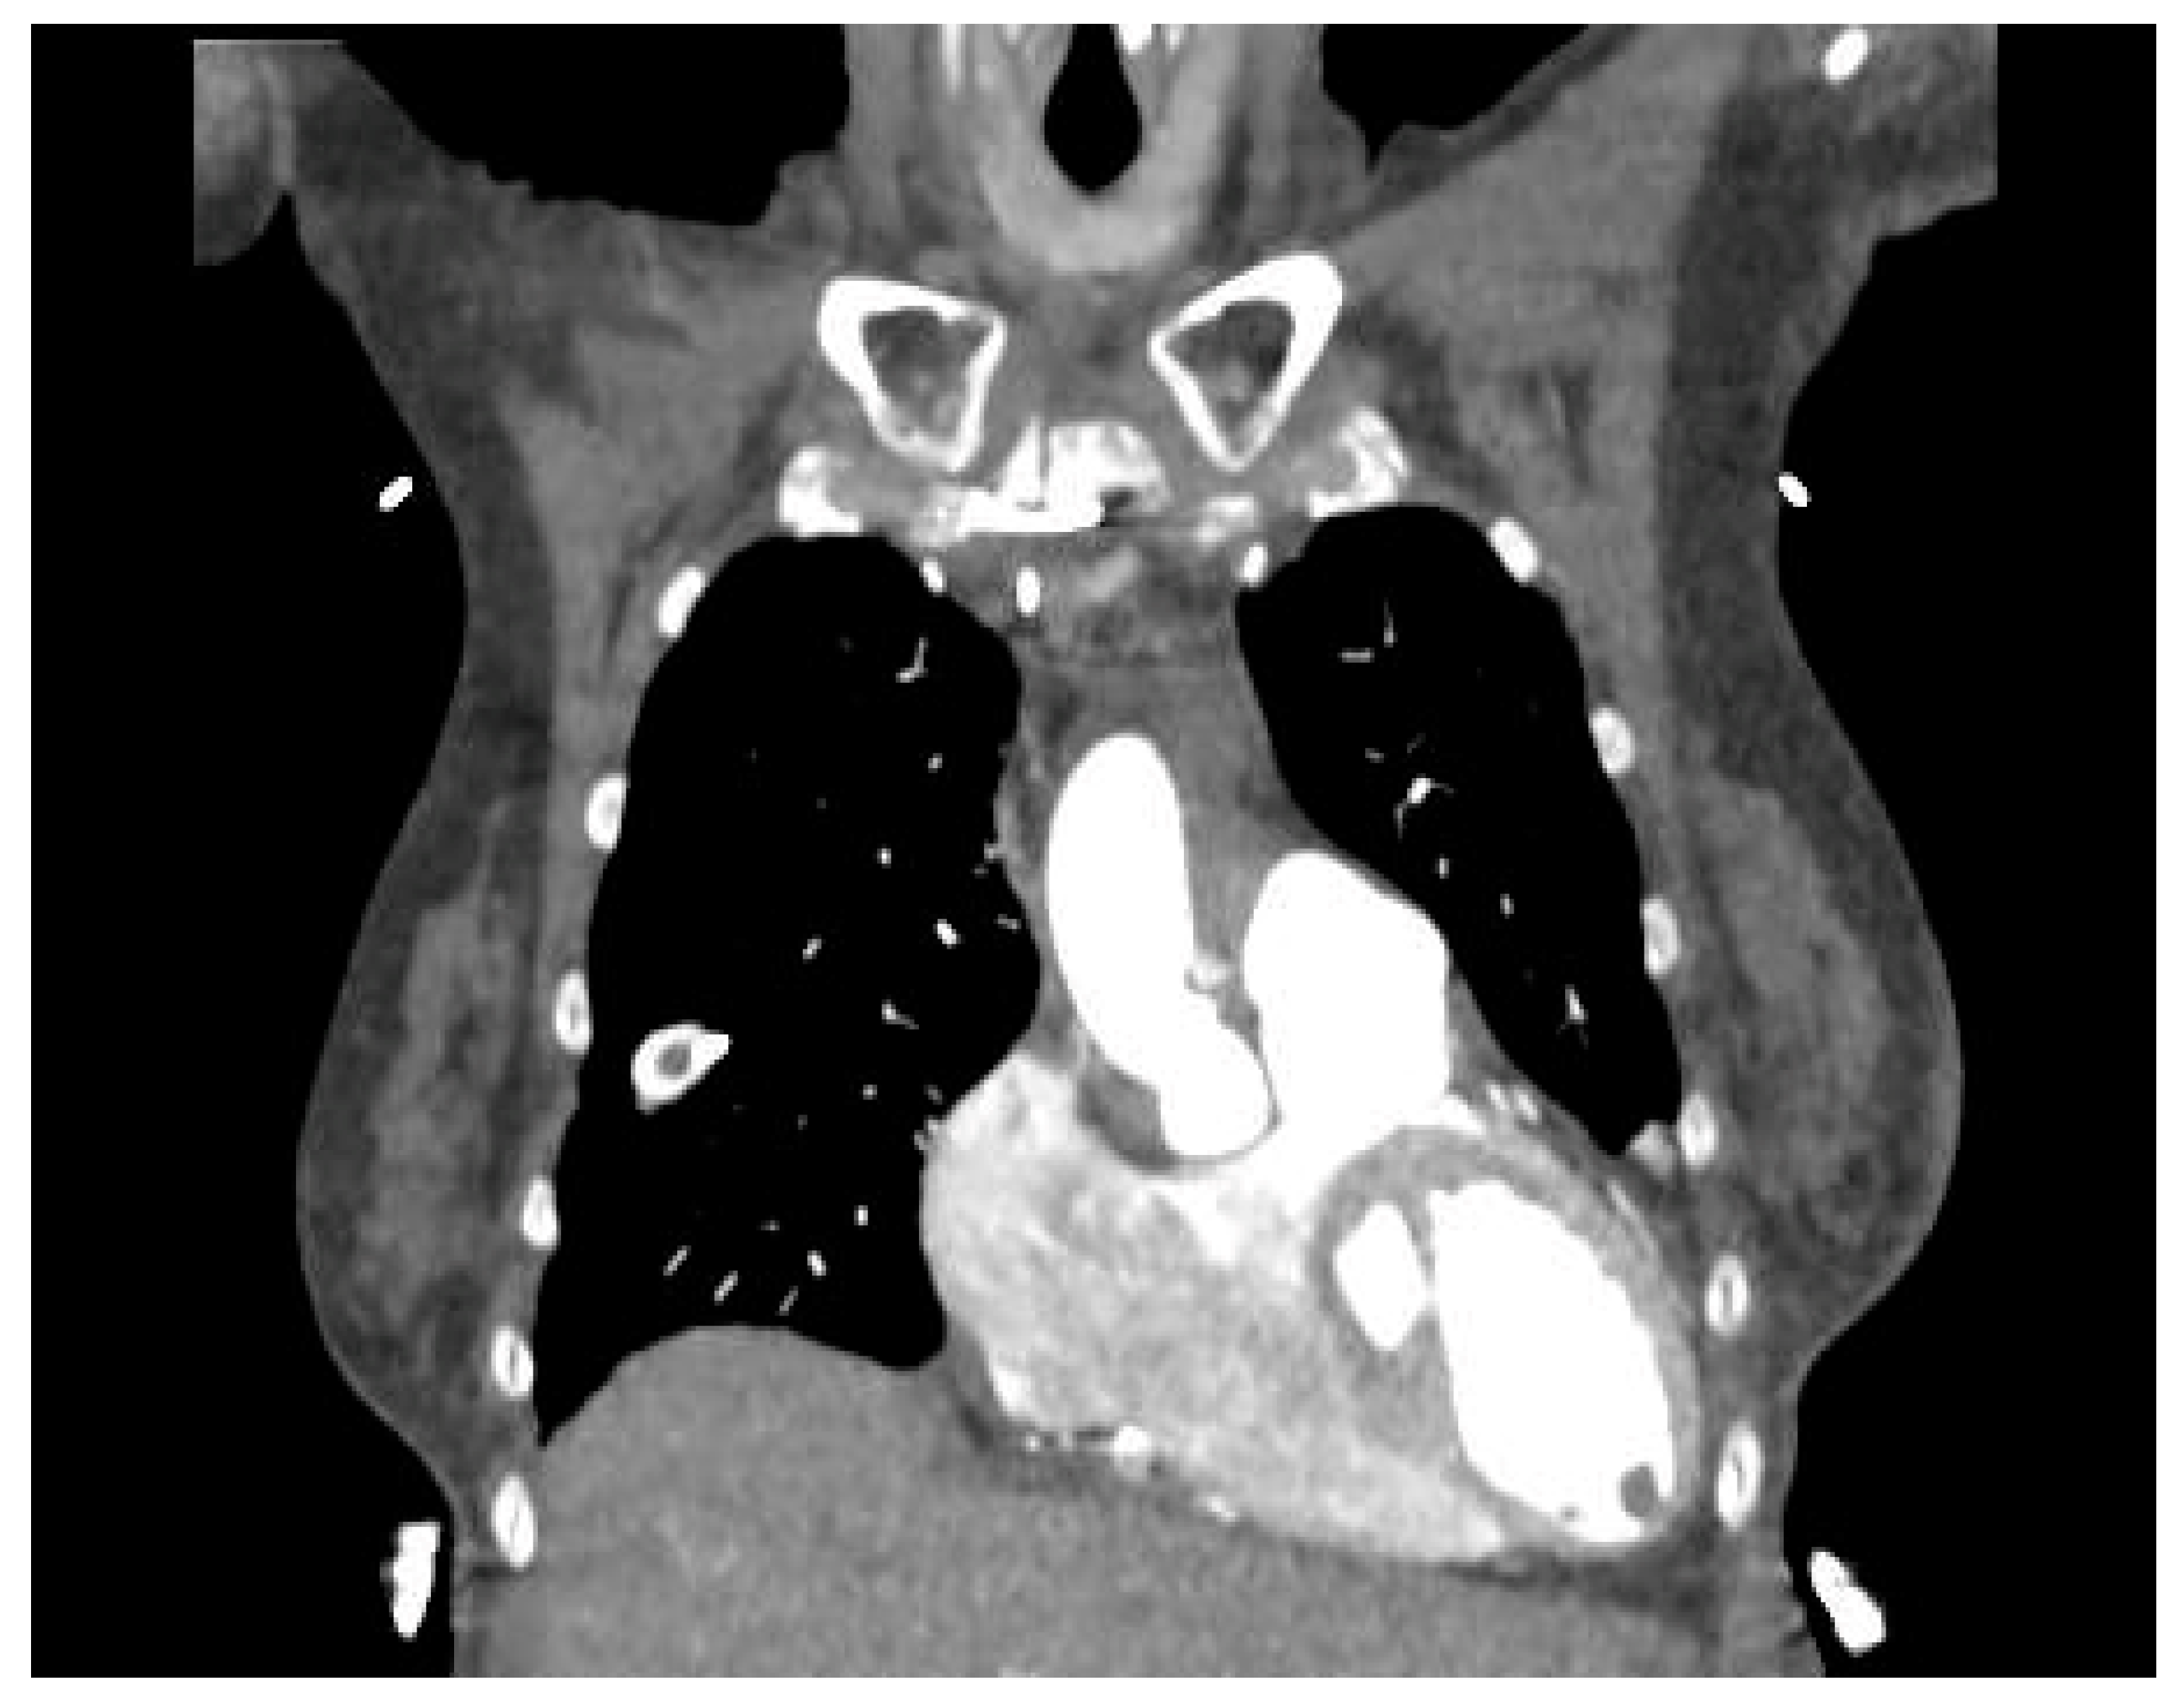

4. Diagnosis

- Zeng, H.; Zhang, M.C.; He, Y.Q.; Liu, L.; Tong, Y.L.; Yang, P. Application of spectral computed tomography dual-substance separation technology for diagnosing left ventricular thrombus. J. Int. Med. Res. 2015, 44, 54–66. [Google Scholar] [CrossRef]

- Bittencourt, M.S.; Achenbach, S.; Marwan, M.; Seltmann, M.; Muschiol, G.; Ropers, D.; Daniel, W.G.; Pflederer, T. Left ventricular thrombus attenuation characterization in cardiac computed tomography angiography. J. Cardiovasc. Comput. Tomogr. 2012, 6, 121–126. [Google Scholar] [CrossRef]

- Nakao, Y.; Aono, J.; Namiguchi, K.; Nishimura, T.; Izutani, H.; Higashi, H.; Inaba, S.; Nishimura, K.; Inoue, K.; Ikeda, S.; et al. Usefulness of contrast computed tomography for diagnosing left ventricular thrombus before impella insertion. J. Cardiol. Cases 2020, 22, 291–293. [Google Scholar] [CrossRef]

- Ouchi, K.; Nakamura, F.; Ikutomi, M.; Oshima, T.; Ishiwata, J.; Shinohara, H.; Kouzaki, T.; Amaki, T. Usefulness of contrast computed tomography to detect left ventricular apical thrombus associated with takotsubo cardiomyopathy. Heart Vessel. 2016, 31, 822–827. [Google Scholar] [CrossRef]